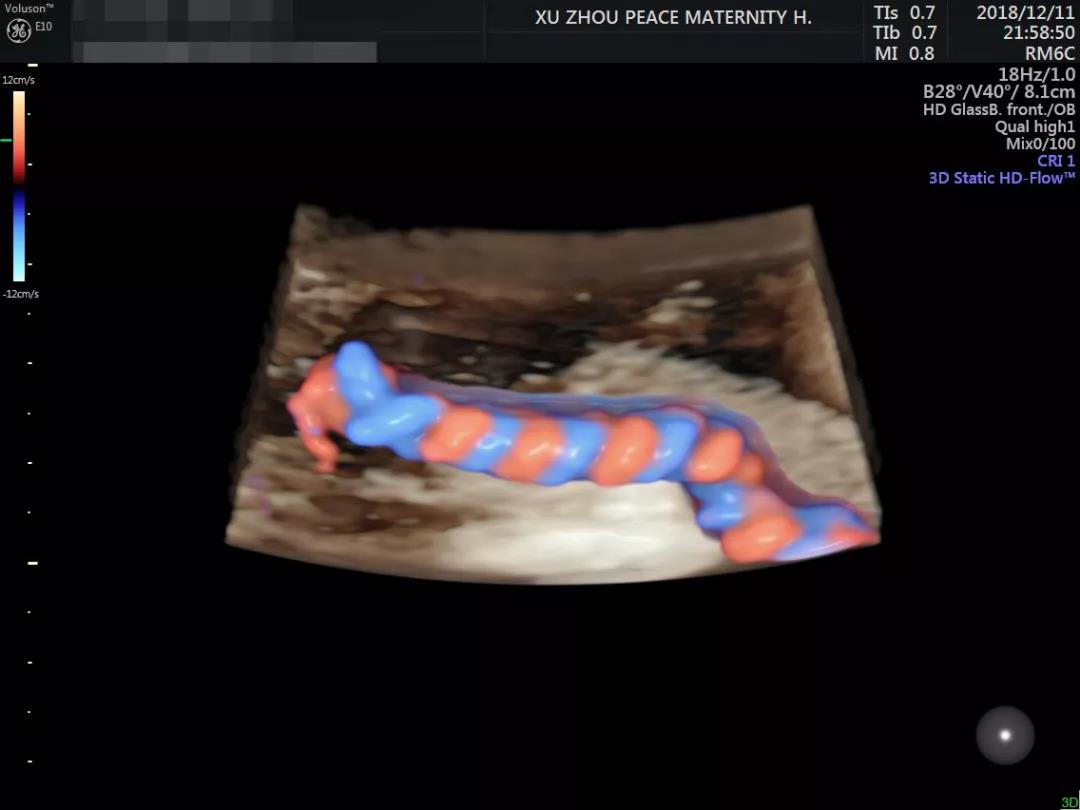

你如果看过邱博士做出的彩超图片

就明白为啥预约这么火爆了

▼

邱博士细致、严谨的工作态度再加上

操作美国GE-E10彩超设备的精湛技术